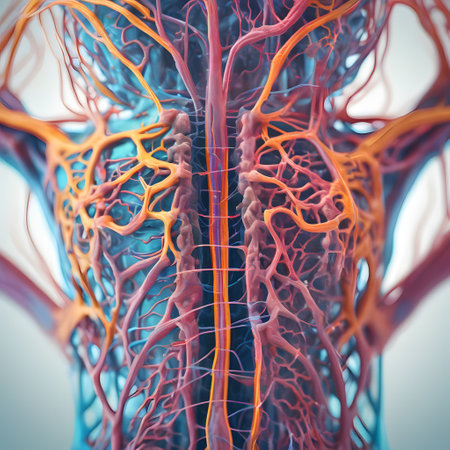

3D Illustration Concept of Central Organ of Human Nervous System Brain Anatomy

Illustrating the role of the central nervous system in processing sensory information and coordinating motor responses.